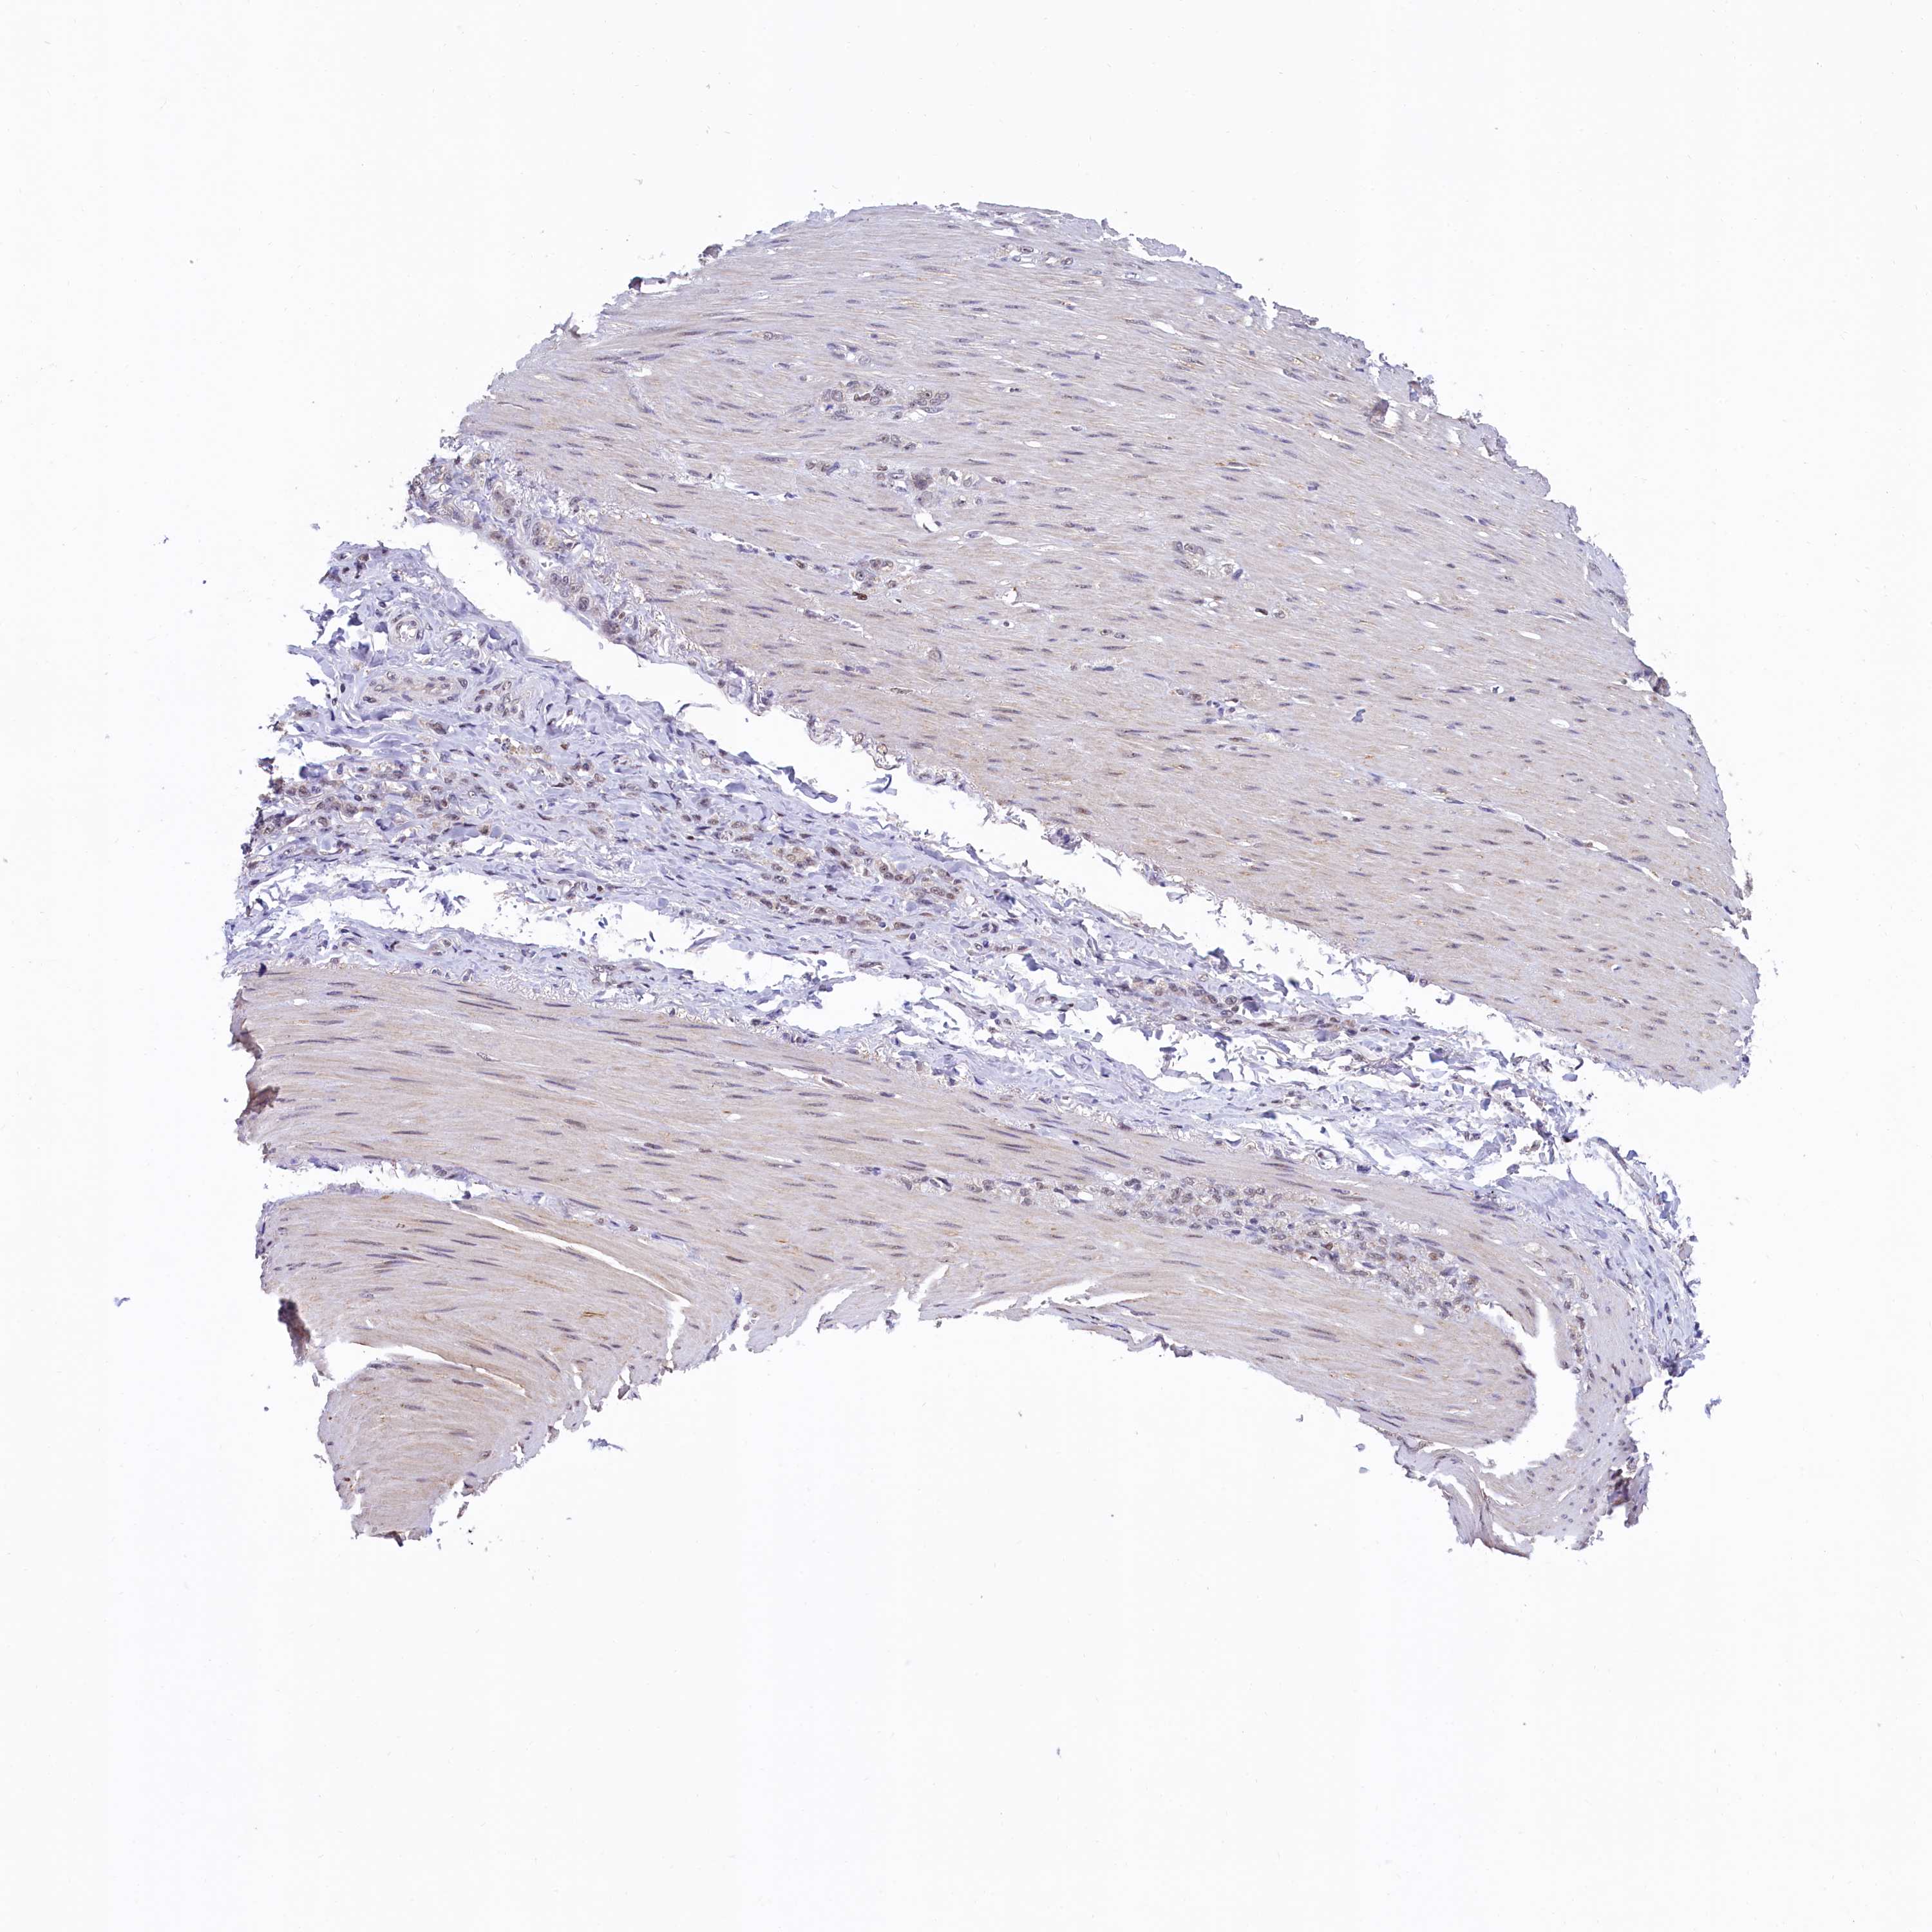

STOMACH CANCER - Protein expressioni

A mouse-over function shows sample information and annotation data. Click on an image to view it in a full screen mode. Samples can be filtered based on level of antibody staining by selecting one or several of the following categories: high, medium, low and not detected. The assay and annotation is described here.

Note that samples used for immunohistochemistry by the Human Protein Atlas do not correspond to samples in the TCGA dataset.

Antibody stainingi

Antibody staining in the annotated cell types in the current human tissue is reported as not detected, low, medium, or high, based on conventional immunohistochemistry profiling in selected tissues. This score is based on the combination of the staining intensity and fraction of stained cells.

Each image is clickable and will lead to virtual microscopy that enables deeper exploration of all samples and also displays staining intensity scores, fraction scores and subcellular localization as well as patient and tissue information for each sample.

Antibody HPA041062

Antibody HPA045473

Staining

High

Medium

Low

Not detected

Intensity

Strong

Moderate

Weak

Negative

Quantity

>75%

75%-25%

<25%

None

Location

Nuclear

Cytoplasmic/membranous

Cytoplasmic/membranous,nuclear

Adenocarcinoma, NOS